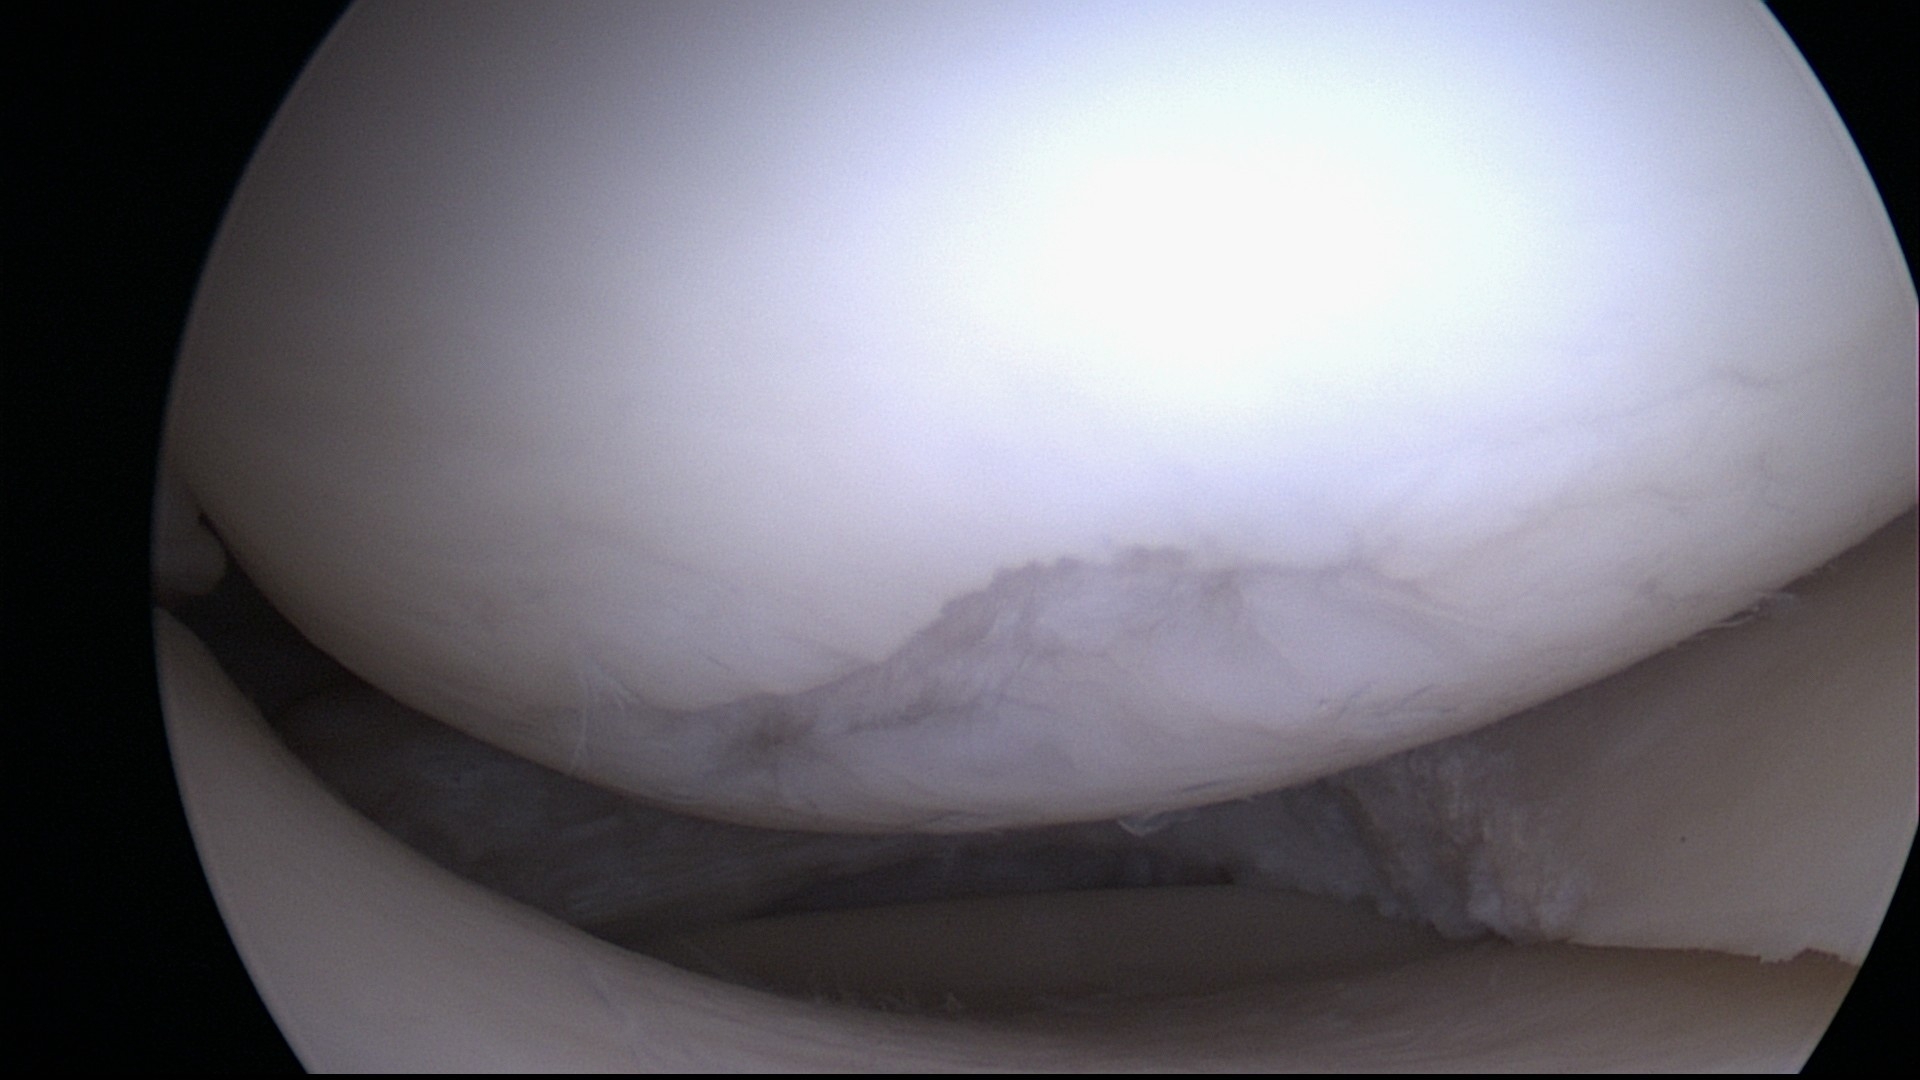

Es gibt fünf Grade der Knorpelschädigung nach Kellgren und Lawrence (Grad 0 bis Grad 4), wobei der Grad der Schädigung nicht direkt die notwendige Therapie vorgibt. Einen ebenso großen Einfluß auf die Therapie hat der Ort der Schädigung, da ein geringer Schaden (Grad 0 bis 2) in einer Hauptbelastungszone (beispielsweise am Knie) große Probleme bei Sport und Belastung verursachen kann, während ein tiefgreifender Schaden des Knorpels an einem Ort ohne Belastung (etwa dem Ellbogengelenk des nicht führenden Armes) sogar unbemerkt bleiben kann.

Abb. 1: 1.-gradiger Knorpelschaden im Knie bei Meniskusriss